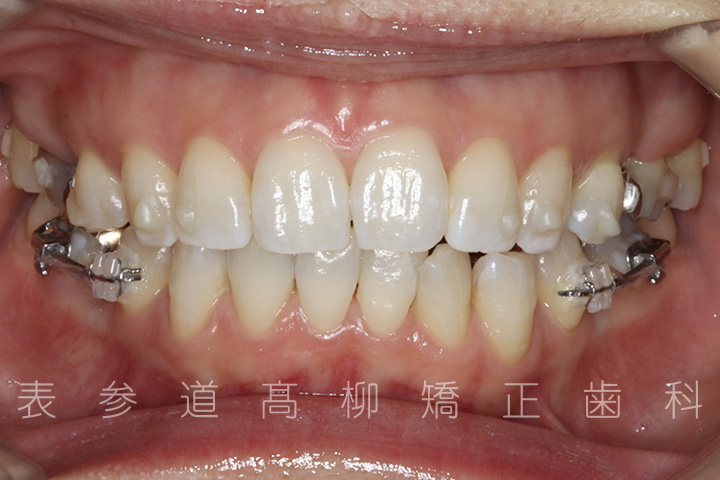

口呼吸と舌癖で前歯が咬み合わない患者様の症例をご紹介いたします。

治療前→治療後

・前歯部開咬

・上顎前突(前歯の前方傾斜)

・上下前歯部叢生(凸凹歯並び)

・口呼吸、舌癖